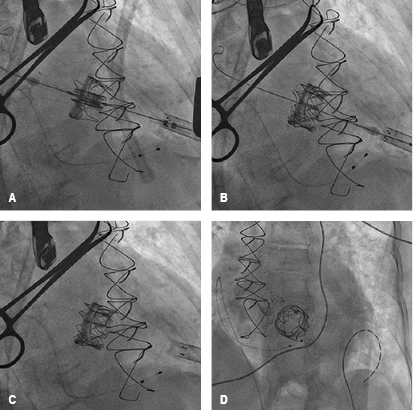

Held on January 22, 2016, prior informed consent of the patient and family. Under general anesthesia with endotracheal intubation, it proceeds to perform asepsis and antisepsis of both femoral regions, with modified Seldinger technique are punctured left femoral artery and right femoral vein, placing introducers of 5 and 6 French (fr), temporary pacemaker is placed in the right ventricle without complications and adequate capture is confirmed, remaining on guard. Then, a left anterolateral thoracotomy is performed at the fifth intercostal space, the pericardium is incised longitudinally and marsupialized, tucks are placed in snuff bag form with prolene 2-0 to expose the left ventricular apex without penetrating ventricular cavity, near the apex and lateral to the anterior descending artery with modified Seldinger technique the apex is punctured at the level of the left ventricle and the femoral introducer 6 fr is advanced, the mitral bio-prosthetic valve is intersected with a 0.035 mm teflonated guidewire with interchange curve, the multipurpose catheter 1.5 fr is advanced through which a guide "Amplatz extra-stiff" is swapped to the left pulmonary vein (Figure 6), introducer Ascendra of 24 fr is placed and through this the delivery transapical system with an Edwards Sapien #26 (Edwards Lifesciences, Irvine, California) valve, after corroborating the proper position with fluoroscopy in right anterior oblique projection, the valve is released successfully (Figure 7). Transesophageal echocardiography performed during the procedure shows the dysfunctional prosthetic mitral valve with a mean gradient of 25 mmHg, the apex is located for the surgical intervention, and is verified in two and four cameras projection, coaxiality with needle and introducer is verified, biological prosthetic valve is intersected with guide and introducer, the deployment of percutaneous mitral valve on longitudinal axis of 3 cameras (120o) is monitored, and the proper position of the valve is verified, without identifying paravalvular leak, appropriate opening/closure and mean gradient of 3 mmHg (Figure 8). Introductors and delivery system are removed, the apex is closed by knotting the two sutures in bag snuff previously set, a pericardial effusion was shown by transgastrical projection, restricted exclusively to posterior wall without hemodynamic effects on right cavities, monitoring is performed by subcostal window observing a separation of sheets of 15mm, repair apex was performed with prolene 2-0 due to a left ventricle tear, contained without further complication; pericardium and chest wall is closed in layers, prior echocardiography subcostal drain is placed, and pacemaker is maintained with stimulation. Fluoroscopy time of 24 minutes, use of 22 milliliters of contrast, removing introducers and considering the procedure as successful.

Figure 6: Step by step of transcatheter mitral valve-in-valve implantation via a transapical approach: mitral bio-prosthetic valve in situ, seen by fluoroscopy (A). Mitral bio-prosthetic valve intersected by "Amplatz extra-stiff" guidewire and advanced to the left pulmonary vein (B). Ascendra introducer is placed and through this the delivery system (C and D).

Figure 7: Step by step of transcatheter mitral valve-in-valve implantation via a transapical approach: an Edwards Sapien #26 valve (Edwards Lifesciences, Irvine, California) is positioned within the Carpentier-Edwards biological valve #27 (A), successfully deployed (B), removing delivery system (C) and corroborating the proper position with fluoroscopy in right anterior oblique projection (D).